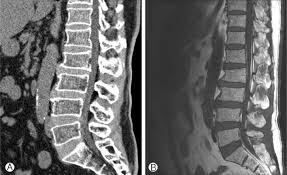

Acute And Chronic Vertebral Compression Fractures Clinical Mri

Acute And Chronic Vertebral Compression Fractures Clinical Mri from clinical-mri.com

Injury To The Vertebral Endplate Disk Complex Associated With Osteoporotic Vertebral Compression Fractures American Journal Of Neuroradiology

Injury To The Vertebral Endplate Disk Complex Associated With Osteoporotic Vertebral Compression Fractures American Journal Of Neuroradiology from www.ajnr.org